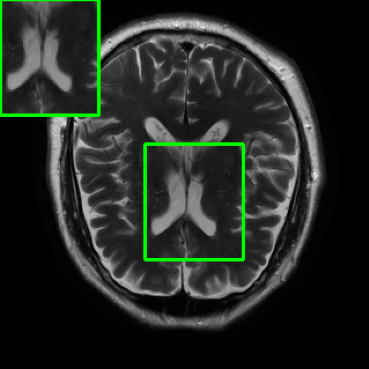

Performance on Data with Lesions: While the previous experiment allowed comparing reconstruction quality with or without planted features, here we test our method on MRI scans with lesions, which are often regions of abnormal or diseased tissue. We utilize the annotated fastMRI+ data666https://github.com/microsoft/fastmri-plus/tree/main to evaluate our method’s image reconstruction capabilities, and compare its outcomes with established baselines. For the training phase, the non-lesion dataset was employed for the global training approach with images whereas LONDN-MRI used adaptively selected images for training (searched from images). In contrast, during the testing phase, we used scans with lesions. The results, as displayed in Table V, indicate that our method achieves substantially higher PSNR values in comparison to the globally trained baseline as well as the LORAKI method. Furthermore, visualizations in Figure 16 clearly demonstrate the superiority of our method, particularly in the nonspecific white matter lesion areas. Thus, both in terms of visual assessment and PSNR values, our approach outperforms the existing baselines and aligns more closely with the ground truth.

| Ground Truth | LORAKI | Global | LONDN-MRI | LONDN-MRI | Oracle |

| (1 iteration) | (2 iterations) | ||||

![]() |

| PSNR = dB | PSNR = 31.45 dB | PSNR = 32.15 dB | PSNR = 32.72 dB | PSNR = 33.15 dB | PSNR = 33.22 dB |